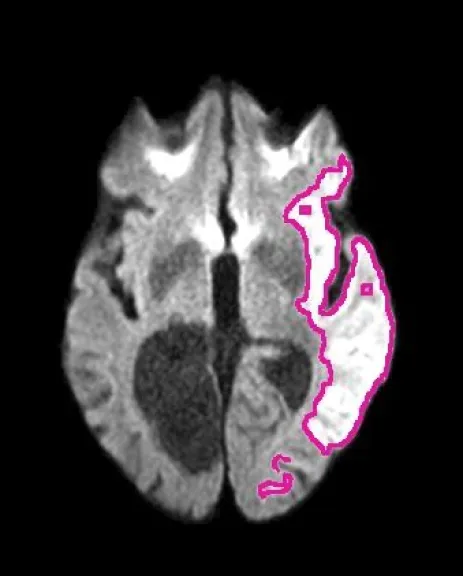

Imagen de resonancia magnética cerebral que muestra, delineada en rosa, el área afectada por un accidente cerebrovascular isquémico, detectada automáticamente por el algoritmo DeepISLES. Foto (Gentileza Ezequiel)

La imagen muestra, en rosa, el área afectada por un accidente

cerebrovascular isquémico, detectada automáticamente por DeepISLES.